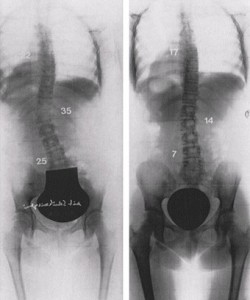

15-godišnja djevojčica sa lijevom lumbalnom i desno torakalnom zakrivljenošću. Nakon 6 sedmica tretmana Schroth metodom smanjenje krivine izraženo u stepenima (desno)